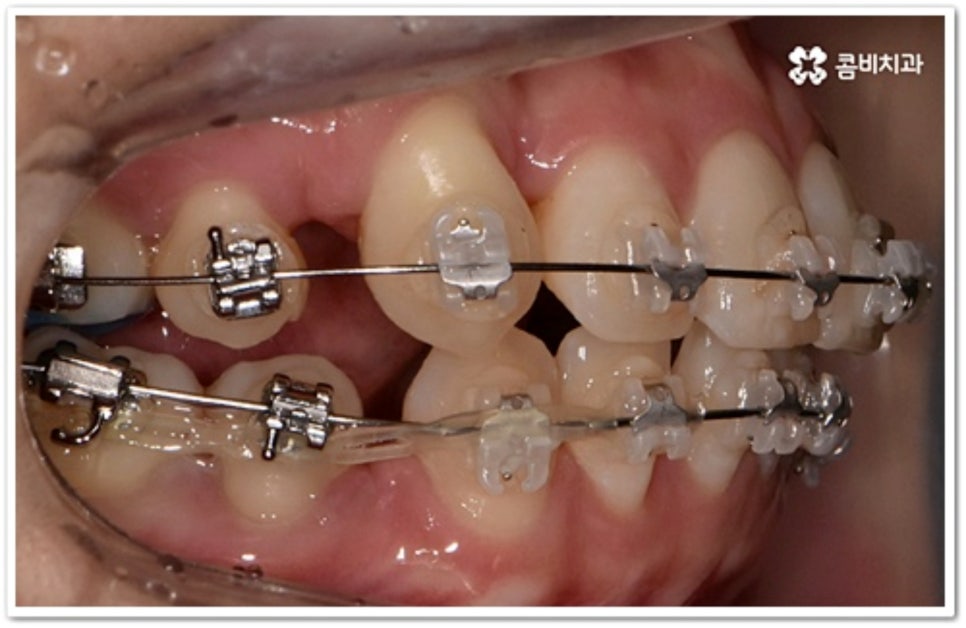

그러나 만약 덧니가 많고 부정 교합 정도가 심하거나 치아가 고르게 배열될 공간이 크게 부족하다면 덧니 발치 교정 치료를 진행하게 되는데, 이때 보통 치아 중에 기능이 가장 적은 소구치를 우선적으로 발치하게 되지만 (사진에서 확인할 수 있는 케이스) 환자분들의 상황에 따라 필요 없는 사랑니를 발치하고 어금니부터 뒤로 밀어 자리를 잡아주거나 충치 또는 짧아진 치근 등으로 심하게 손상된 치아가 있는 소구치를 우선적으로 발치하여 교정 치료를 진행하기도 하고, 필요시 임플란트와 병행하여 치료를 진행하는 경우도 있습니다. 따라서 먼저 자신의 상황에 대해서 면밀하게 검진을 받아보고 자세한 치료 계획에 대해서 의료진과 충분하게 상담해 보시는 게 좋을 거예요.

송곳니는 끝이 뾰족하여 질긴 음식을 잘게 찢는 데 용이하며 씹을 때 아래턱의 움직임을 조절해 주는 등 저작 기능을 원활하게 수행하는데 큰 도움을 주고 있습니다. 또한 뿌리가 길고 크기가 커서 주변 치아 지지 및 치열과 안모의 형태를 잡아주는데 중요한 역할을 하기 때문에 뽑지 않고 위치만 제자리로 이동시켜 상하악 균형을 맞추면서 턱관절을 관리하는 방식으로 덧니 발치 교정 치료를 진행하고 있는데요. 이때 입 모양이나 턱의 각도, 안모의 조화를 전체적으로 고려하지 않고 무리하게 덧니 발치 교정을 하게 되면 합죽이나 옥니와 같은 부작용을 낳을 수 있으니 주의할 필요가 있어요.

치아는 제자리로 돌아가려는 성질을 가지고 있어서 덧니 발치 교정이 끝난 후 일정 기간 동안은 유지 장치를 착용하여 이를 예방하고 정기 검진을 꼬박꼬박 받으면서 사후 관리를 철저하게 해 주는 게 좋을 거예요. 유지장치에는 고정식과 가철식이 있는데 치아 안쪽에 얇은 철사를 붙이는 고정식 (사진에서 볼 수 있는 사례) 은 앞니가 틀어지는 것을 방지해 주고, 뺐다 꼈다 하는 가철식은 교정 치료할 때 악궁 확장을 한 경우 전체 치열을 유지하기 위해 필요한 방식이라고 할 수 있어요. 환자분들 각각의 치료 과정이나 구강 상태에 따라 둘 중 하나를 선택하거나 두 가지 다 해야 하는 경우가 생길 수 있습니다.